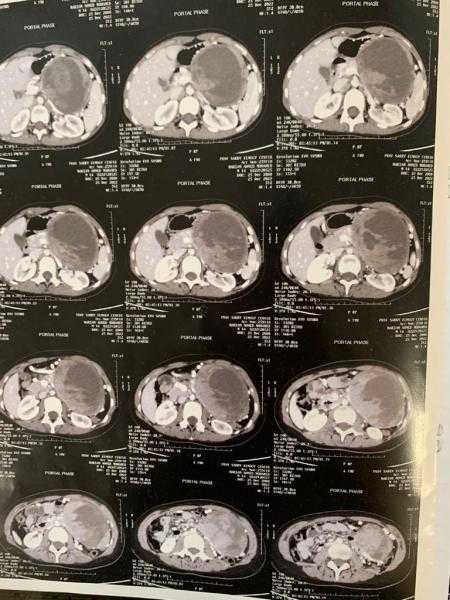

نجح فريق طبي بجامعة المنصورة، برئاسة الدكتور أمجد فؤاد رئيس أقسام الجراحة بكلية الطب من اجراء جراحة دقيقة وشديدة التعقيد لطفلة صغيرة تبلغ من العمر 14 عاما، كانت تعانى من ورم سرطانى...